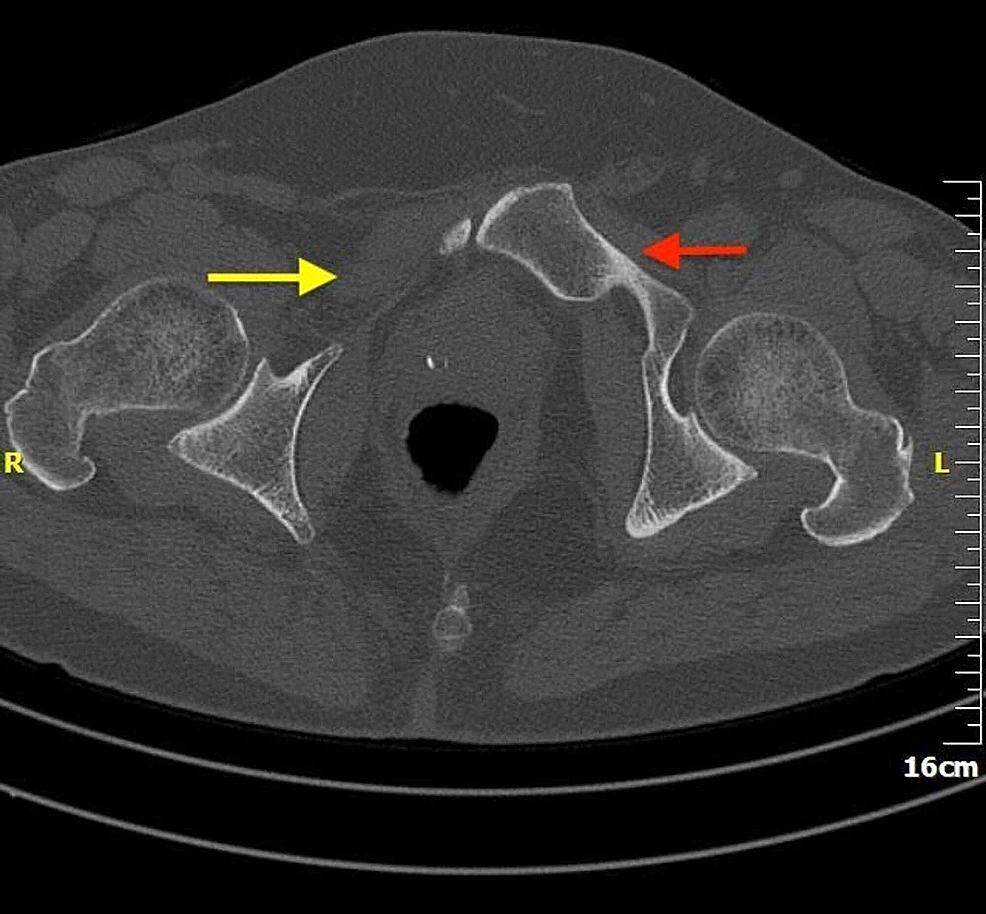

Cureus | Pubic Bone Aplasia as an Incidental Finding in the Adult …